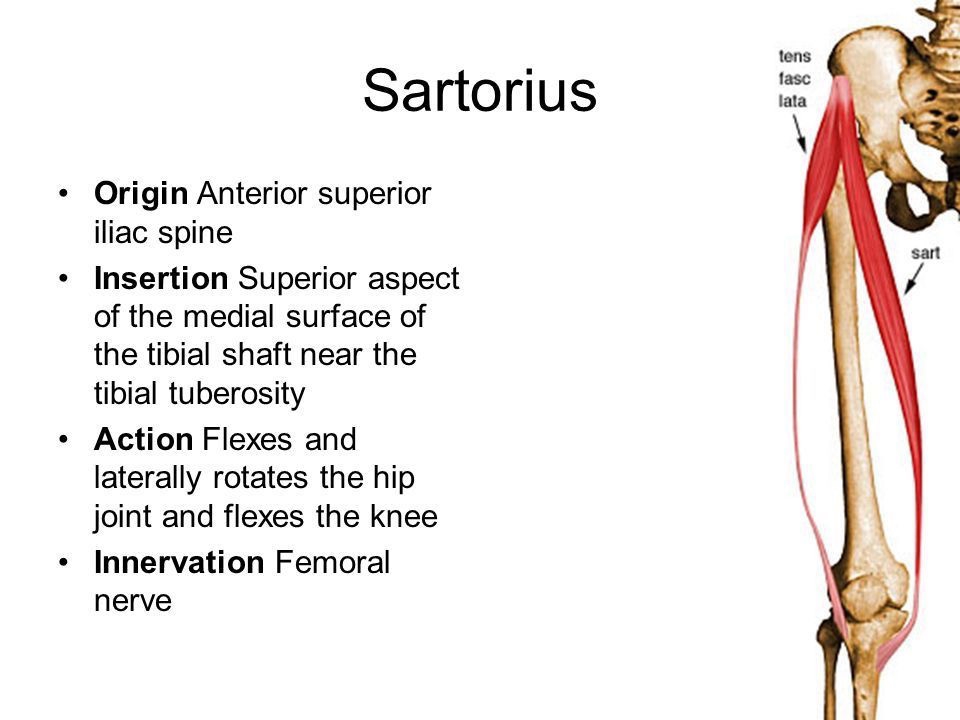

縫工筋 (Sartorius)

縫工筋 (Sartorius)